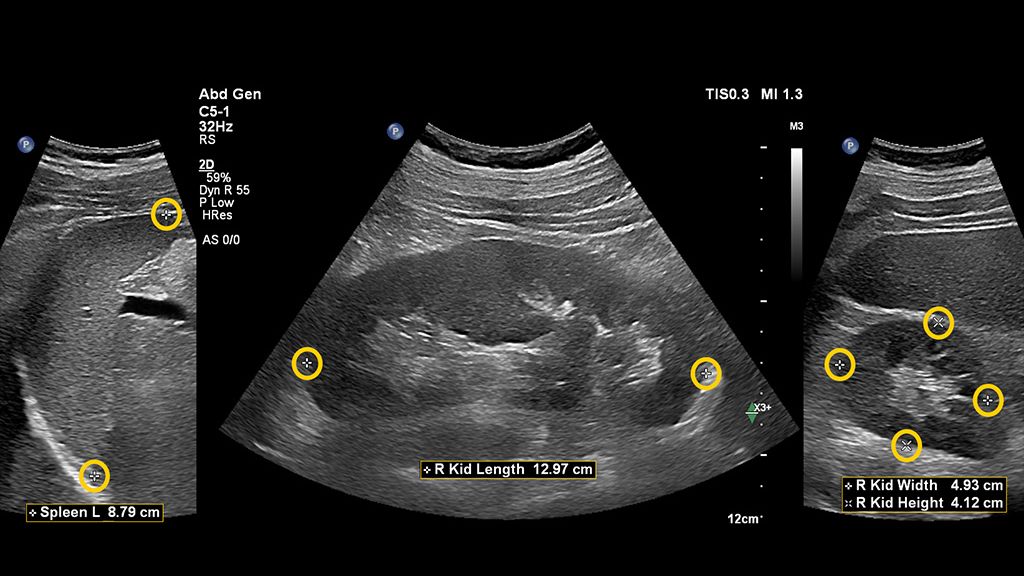

AI-driven Auto Measure Abdomen - Philips